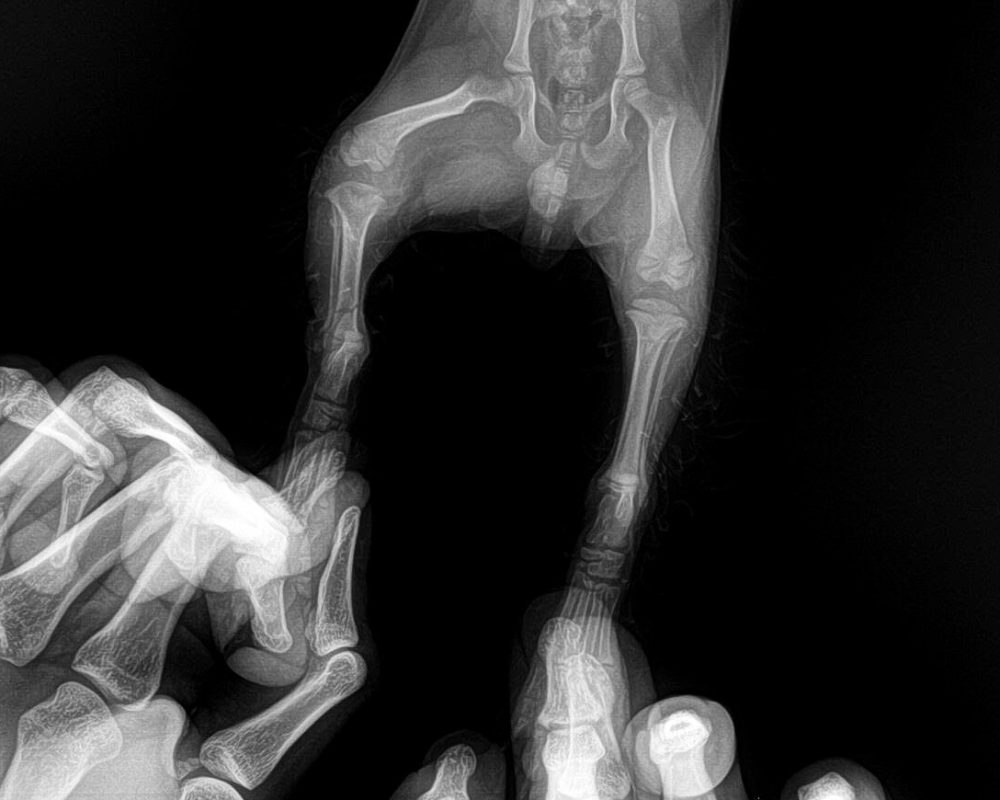

✔ Chụp X-quang chân sau

Kết quả X-quang cho thấy:

Gãy xương chân sau bên phải

👉 Đây là tổn thương thật sự, không phải bong gân hay trầy xước phần mềm như nhiều chủ nuôi thường nghĩ.